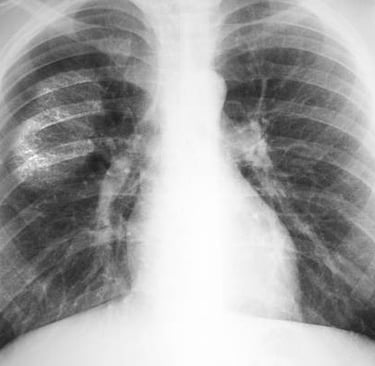

Diagnosis of ILD requires a careful and thorough evaluation by a pulmonary specialist. A detailed medical history is essential, including information about occupational exposures, medication use, family history, and underlying health conditions. Imaging studies, especially high-resolution CT (computed tomography) scans, are critical for visualizing patterns of scarring or inflammation in the lungs. Pulmonary function tests are used to assess how well the lungs are working. In some cases, a lung biopsy may be necessary to obtain a sample of lung tissue for further analysis. Blood tests and bronchoscopy (a procedure that uses a camera to look inside the lungs) may also help pinpoint the specific cause. Early and accurate diagnosis is essential for guiding treatment and slowing the progression of the disease.